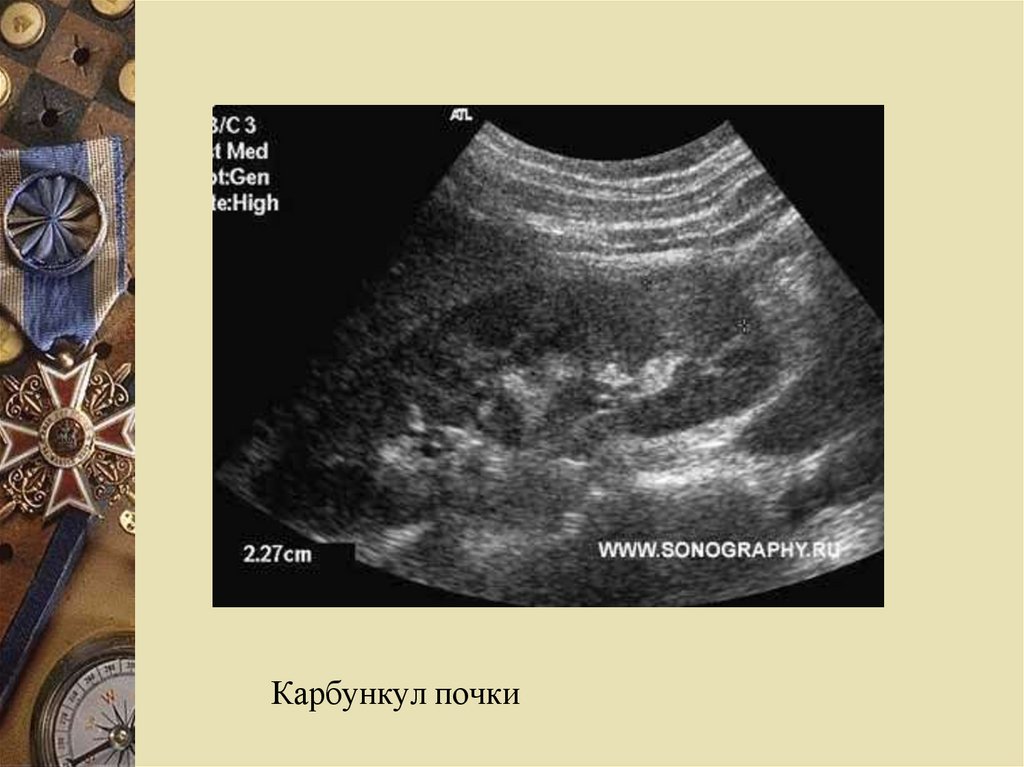

Карбункул почки: гипоэхогенный участок без

четких контуров, иногда выбухание внешнего

контура почки в этом месте

Карбункул почки